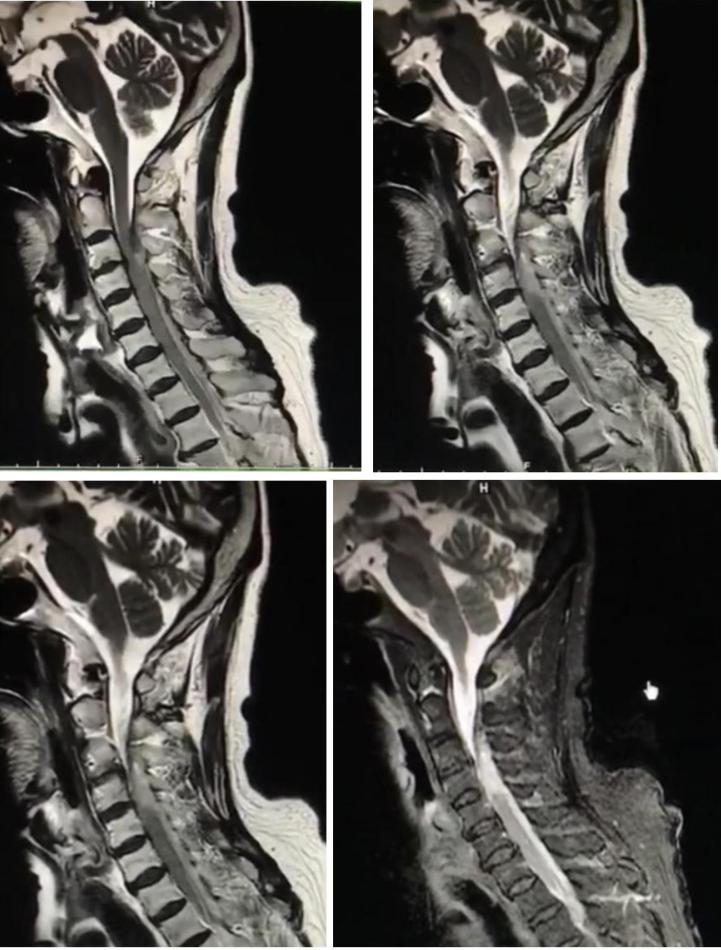

病例9

老年女性,急性起病,突发颈后部疼痛伴右侧肢体麻木无力,右侧肢体肌力2级。

答案:脊髓硬膜外血肿。补充病史既往长期服用华法林。患者临床以麻木,肢体无力卒中样起病。但是有颈部疼痛病史,病史跟影像提示脊髓硬膜外血肿。脊髓硬膜外血肿可能是自发的,也可能是继发于创伤、凝血功能障碍或麻醉操作。危险因素包括高龄、女性、创伤、血管畸形、抗凝治疗和高血压。提醒注意的是这样的患者有可能在绿色通道中被当做急性卒中患者被溶栓。